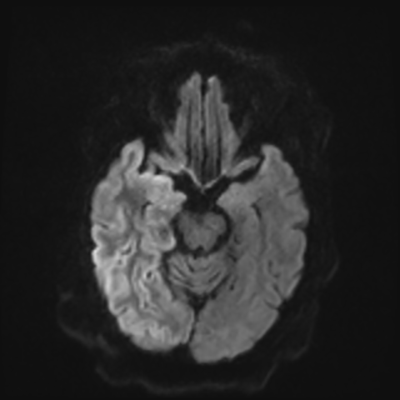

You come back the next day and see how things are going. The patient's electrographic record has shown a moderate encephalopathy (diffuse slowing, disorganization) with frequent right posterior quadrant delta slowing. Based on this result, and an adequately improved clinical examination, you give the okay to proceed with obtaining an MRI of his brain. This is shown below.

MRI brain (DWI)